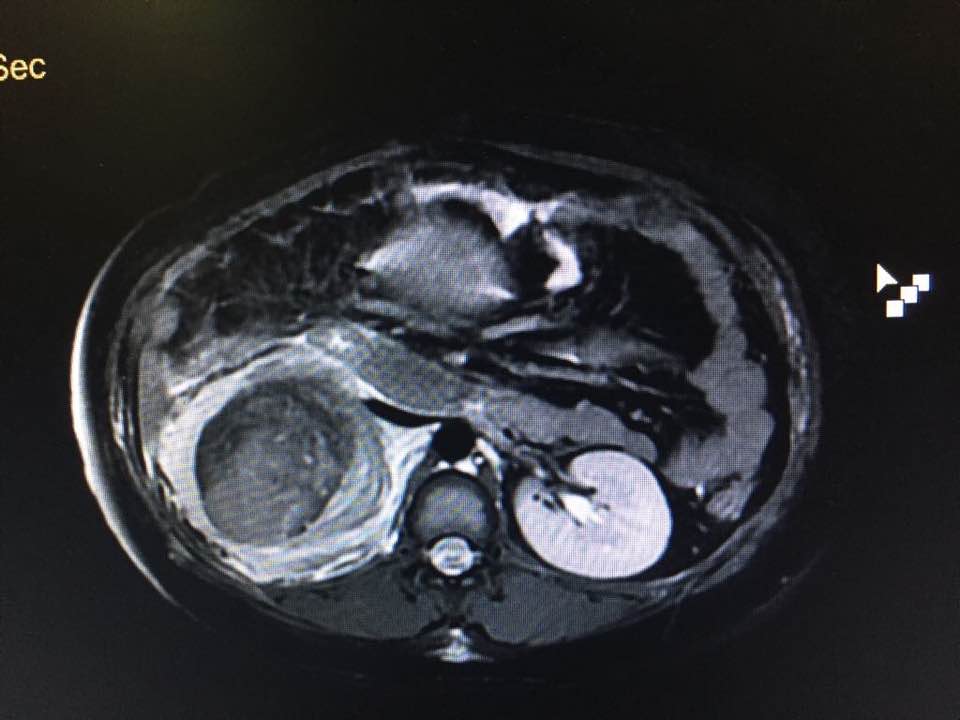

A 33 weeks pregnant patient with right renal Angiomyolipoma presented with pain in right flank. In MRI it was found that the tumour in her kidney was bleeding. She was immediately shifted to operation-theatre and Cesarean was operated with right radical Nephrectomy and salvaged. Now both mother and baby doing fine.